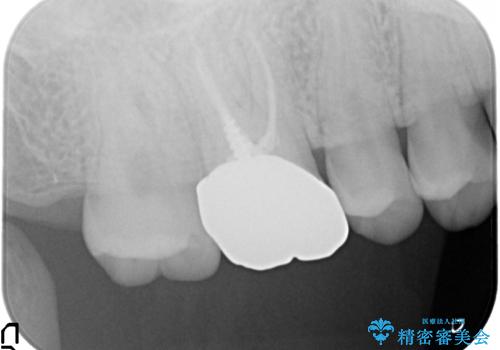

- 見た目が気になるため右上6のゴールドクラウンをセラミックにしたいといらっしゃった方の症例です。

再根管治療を御希望されたため根管治療を行った後、メタルボンドクラウンによる補綴を行いました。

金属フレームを用いたメタルボンドクラウンは、オールセラミッククラウンに比べ審美性で劣るというイメージが強いです。しかし歯肉の下までしっかりと被せれば、唇・頬側からは金属部が見えず、十分に審美的です。

また適合もよく、強度も高いので、奥歯の補綴には適したクラウンです。